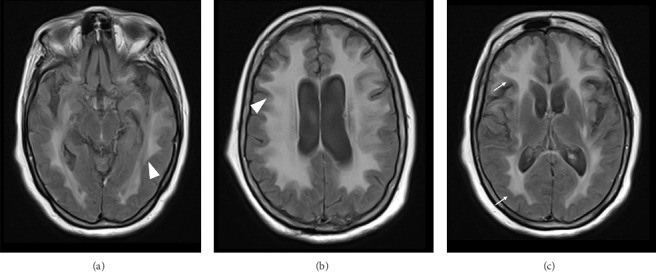

Introduction: Gliomatosis cerebri (GC) is a diffuse neoplastic process, whose presentation is extremely rare and lacks a characteristic clinical pattern. The objective of this case is to describe the clinical aspects of a patient with GC, in whom symptoms of parkinsonism and neurocognitive issues predominate. Case Report: A 78-year-old patient with no significant medical history was referred to the neurology consultation due to balance disturbances accompanied by head tremor. Symptoms of parkinsonism progressively worsened, adding cognitive and neuropsychiatric disorders. Cranial magnetic resonance imaging (MRI) showed diffuse and generalized white matter hyperintensity. Under the suspicion of GC, a frontal lobe biopsy was performed, with a pathology report of diffuse astrocytoma, thus confirming the diagnosis of GC. Conclusion: GC is a disease that presents with nonspecific clinical manifestations, making a clinical diagnosis challenging. It should be suspected in cases of parkinsonism accompanied by other focal neurological disorders. This leads to delayed diagnosis and consequently low incidence. The importance of MRI as a diagnostic aid is highlighted, with biopsy being necessary to confirm the diagnosis.

脑胶质瘤病(Gliomatosis cerebri, GC)是一种弥漫性肿瘤,其临床表现极为罕见,缺乏特征性的临床模式。本病例的目的是描述GC患者的临床方面,其中帕金森症状和神经认知问题占主导地位。病例报告:一名78岁无明显病史的患者,因平衡障碍伴头部震颤而就诊神经内科。帕金森氏症的症状逐渐恶化,增加了认知和神经精神障碍。颅脑磁共振成像显示弥漫性广泛性白质高信号。在怀疑为胃癌的情况下,行额叶活检,病理报告为弥漫性星形细胞瘤,确诊为胃癌。结论:胃癌是一种临床表现非特异性的疾病,临床诊断具有挑战性。在帕金森病合并其他局灶性神经系统疾病的病例中应怀疑。这导致诊断延迟,从而降低发病率。MRI作为诊断辅助的重要性被强调,活检是必要的,以确认诊断。